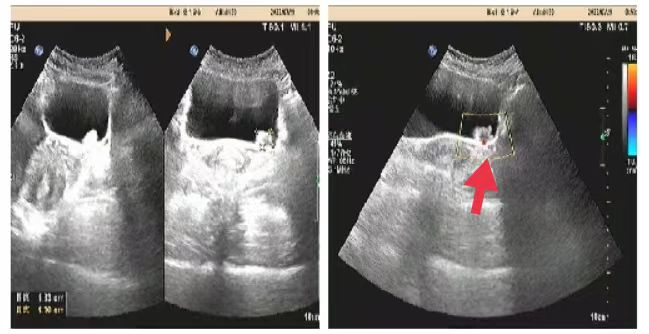

05、**女士,54岁

于2023年8月16日在邯郸仁泰东区体检,膀胱彩超检查提示:膀胱内可见高回声团1.8*1.4cm,边界欠清、形态不规则,内回声不均匀,随体位改变移动不明显。CDFI:周边可见少量血流信号。2023年8月17日首次回访,通知客户到三甲医院进一步检查。2023年8月30日跟踪回访,客户家属告知,在北大医院复查,结果与我院一致,已在北大医院完成手术治疗,现出院在家休养。